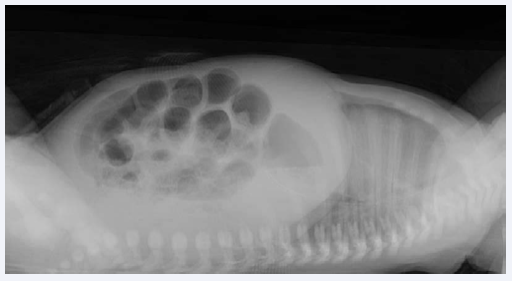

On day four, the nasogastric tube started draining small amounts of gastric content prior to feeds and he started passing dark stools, guaiac-positive. On the seventh day of life, despite stable vital signs and no supplementary oxygen requirement, the clinical condition worsens, with lethargy, persistent vomiting and abundant bilious gastric drains. The abdomen was distended, with mild diffuse tenderness, without abdominal wall erythema or visible bowel loops. Laboratory studies found a C-reactive protein level of 4.3 mg/dL (rising from 2.1 mg/dL on day six), a white blood cell count of 26.51 x 103/μL and a platelets count of 363 x 103/μL. A plain abdominal x-ray in supine and lateral decubitus position showed diffusely dilated loops of bowel with air-fluid levels (Figure 1).

Figure 1 A plain abdominal x-ray taken in the seventh day of life showing diffusely dilated loops of bowel with air-fluid levels.